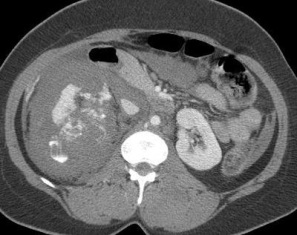

![]() 包括动脉栓塞的非手术处理(Non-operative management,NOM)腹部创伤(visceral trauma),占肝、脾和肾损伤的60%-90%。